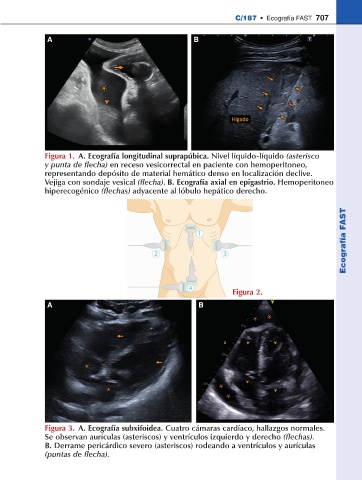

Figura 1. A. Ecografía longitudinal suprapúbica. Nivel líquido-líquido (asterisco

y punta de flecha) en receso vesicorrectal en paciente con hemoperitoneo,

representando depósito de material hemático denso en localización declive.

Vejiga con sondaje vesical (flecha). B. Ecografía axial en epigastrio. Hemoperitoneo

hiperecogénico (flechas) adyacente al lóbulo hepático derecho.

Figura 3. A. Ecografía subxifoidea. Cuatro cámaras cardíaco, hallazgos normales.

Se observan aurículas (asteriscos) y ventrículos izquierdo y derecho (flechas).

B. Derrame pericárdico severo (asteriscos) rodeando a ventrículos y aurículas

(puntas de flecha).